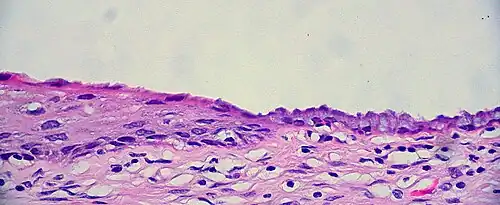

Histology

The cervical canal is generally lined by "endocervical mucosa" which consists of a single layer of mucinous columnar epithelium. However, after menopause, the functional squamocolumnar junction moves into the cervical canal, and hence the distal part of the cervical canal may be lined by stratified squamous epithelium (conforming to a "type 3 transformation zone").[2]